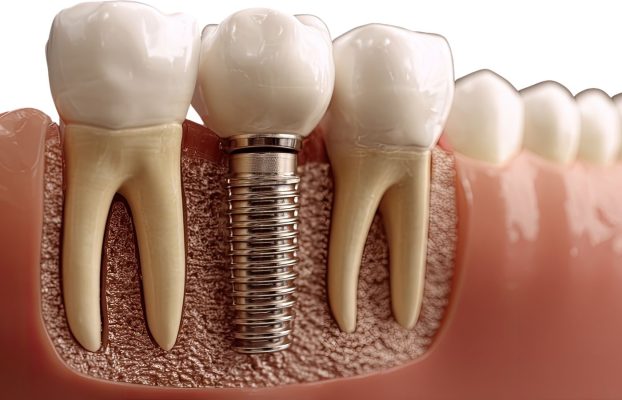

Hai trụ Implant giúp phân bố lực đều, ăn nhai chắc chắn và ổn định như răng thật.

Mỗi trụ Implant kích thích xương tại vị trí mất răng, giúp giữ xương hàm lâu dài.

Implant riêng lẻ giúp từng răng hoạt động độc lập, giảm quá tải và tăng tuổi thọ.